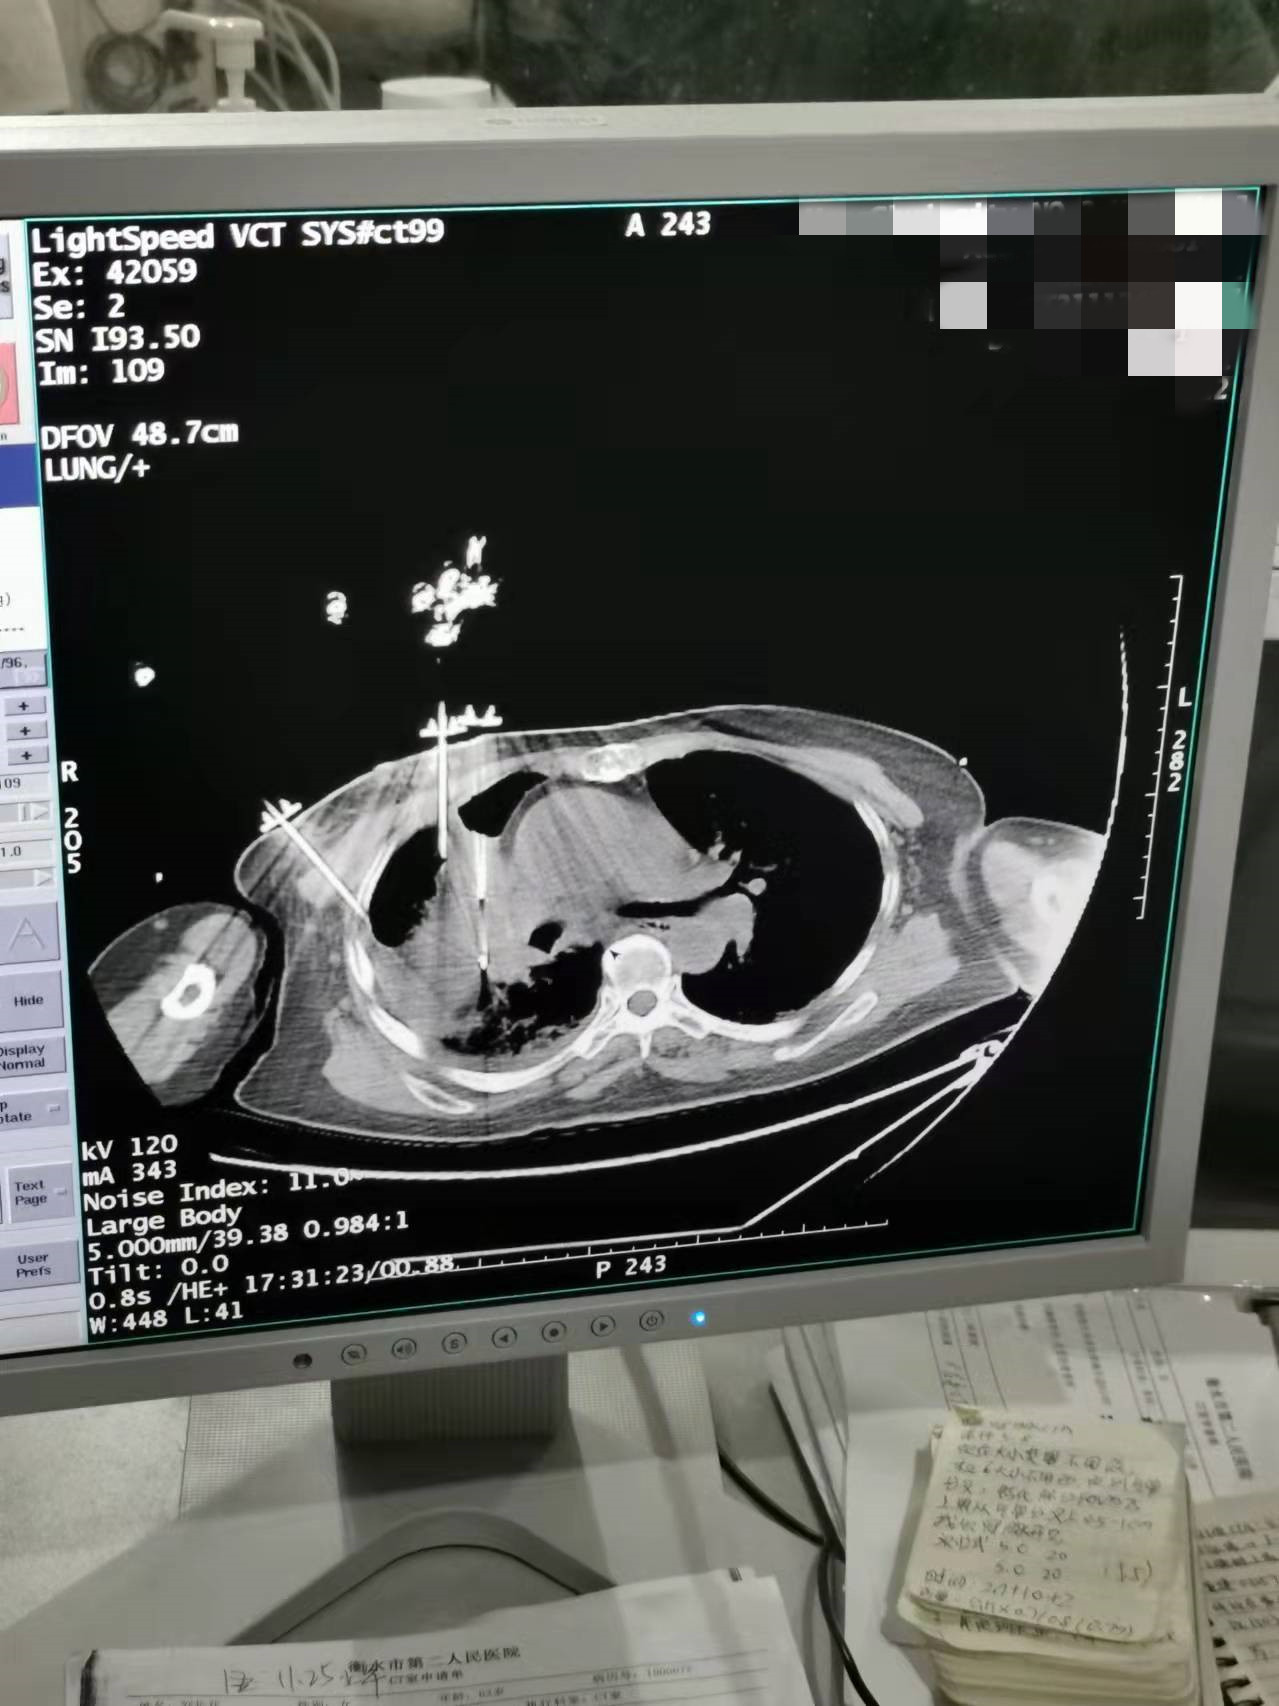

2021年11月份肺部氩氦刀手术

发布人:美国氩氦刀技术官方网站    发布时间:2021/11/26 14:02:23